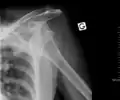

| Anterior dislocation of the left shoulder. | |

In over 95% of shoulder dislocations, the humerus is displaced anteriorly.[7] In most of those, the head of the humerus comes to rest under the coracoid process, referred to as sub-coracoid dislocation. Sub-glenoid, subclavicular, and, very rarely, intrathoracic or retroperitoneal dislocations may also occur.[8]

Anterior dislocations are usually caused by a direct blow to, or fall on, an outstretched arm. The person typically holds his/her arm externally rotated and slightly abducted.

An anterior dislocation of the shoulder

Anterior dislocation of the right shoulder. AP X ray